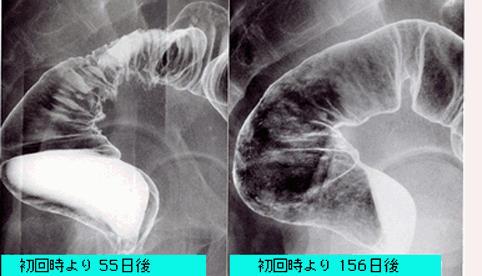

症例提示(所在地,施設名等): 東京都・ 国立がんセンター中央病院と九州がんセンターの共同作成

症例登録日 1999/01/01

疾患(病理主体)の分類炎症性・潰瘍性疾患/その他

部位(臓器別)大腸/直腸

検査方法X-P

病変の最大径(ミリ)40以上